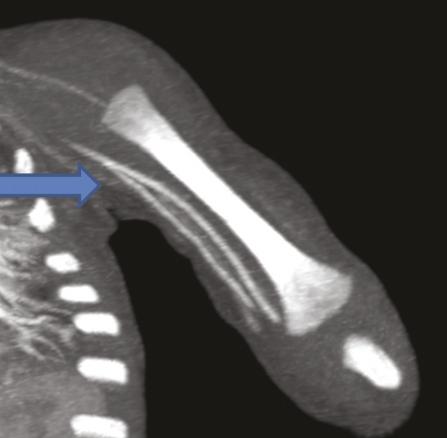

Ce nourrisson de 11 mois était hospitalisé pour l’exploration d’une masse à l’extrémité inférieure de l’avant-bras. À l’échographie, on notait une formation tissulaire hypervasculaire au Doppler couleur, motivant un complément d’investigations. L’imagerie par résonance magnétique étant techniquement difficile à réaliser, un angioscanner a été demandé, qui montrait (fig. 1 et 2 ) une tumeur vasculaire à développement essentiellement sous-cutané respectant les structures musculaires et osseuses. Il mettait en évidence une variante anatomique : une origine haute de l’artère radiale sans cross-over avec l’artère cubitale.

L’artère radiale a une importance médicale majeure : elle permet le monitoring de la pression artérielle en anesthésie et réanimation, elle sert de greffon en chirurgie coronarienne, et constitue un abord essentiel dans les fistules artérioveineuses d’hémodialyse. Selon les études,1 la prévalence estimée de l’origine haute de l’artère radiale, appelée aussi artère radiobrachiale, varie de 4,67 à 15,6 %. Cette particularité est le plus souvent unilatérale, sans prédominance de sexe ou de côté rapportée à l’heure actuelle. Elle peut prendre naissance à plusieurs niveaux, depuis l’artère axillaire jusqu’à l’artère humérale. Le cross-over cubital correspond à une artère anastomotique faisant communiquer l’artère cubitale avec l’artère radiobrachiale. Ce cross-over a été observé dans 17,8 % des cas de naissance haute de l’artère radiale.2 Compte tenu de son importance pour les abords vasculaires, il est important de connaître les variantes anatomiques de l’artère radiale.